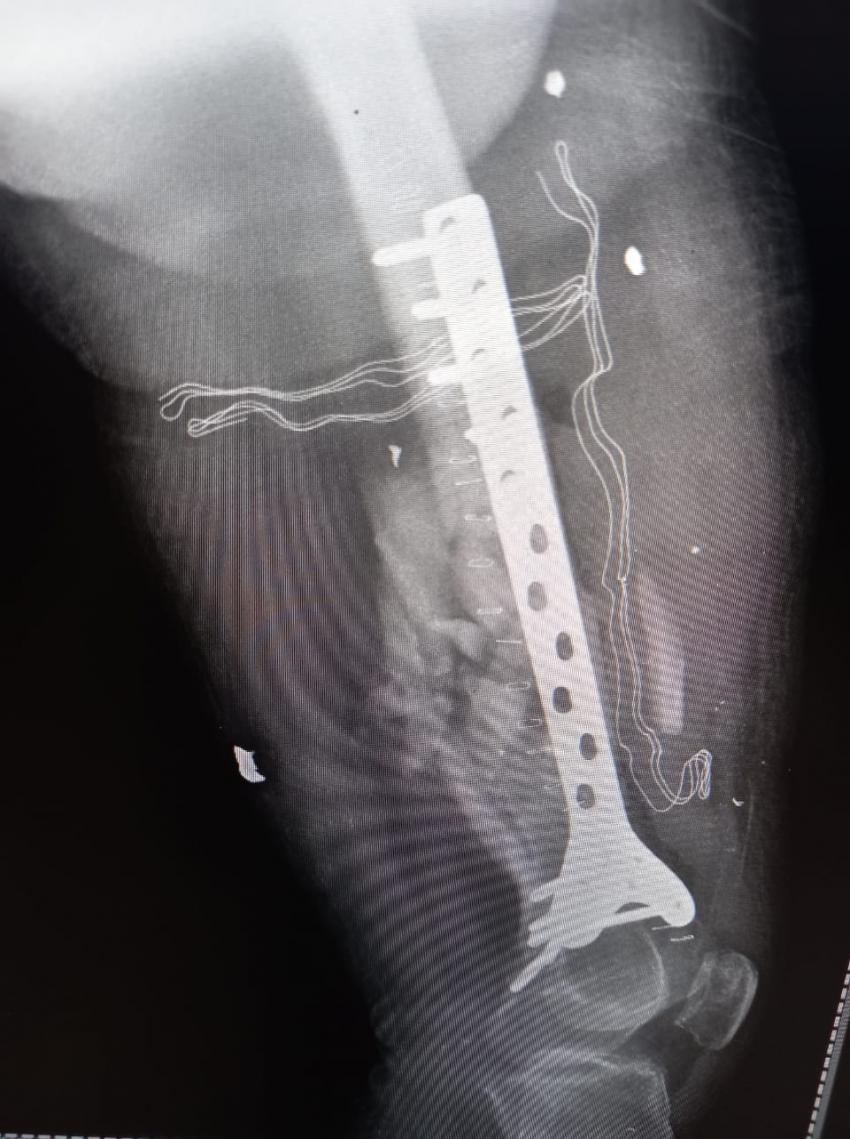

من جانبه بين طبيب جراحة العظام والمفاصل أن المريض كان يعاني من كسر مفتوح في أسفل عظم الفخذ اليمين مما أدى إلى تفتت العظم وتهتك الأنسجة المحيطة به نتيجة الإصابة التي تعرض لها المريض، وتم إجراء عملية جراحية وتركيب صفيحة معدنية وبراغي وإزالة المثبت الخارجي في المستشفى الميداني الأردني لكونه المستشفى الوحيد الذي ما زال مستمراً شمال القطاع.